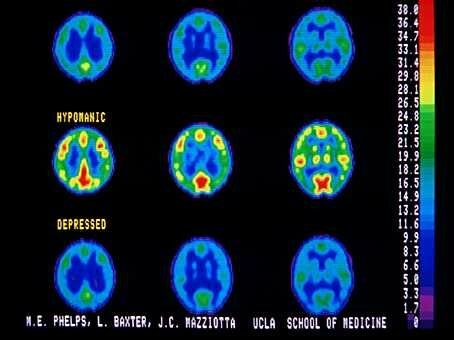

El funcionamiento de los lobulos frontales se asocia con los niveles mas elevados de la funcion cortical, entre los cuales se encuentran los inherentes a la actividad intelectual. Zemetkin y colaboradores, demostraron un aprovechamiento menor de glucosa en areas cerebrales frontales a traves de los estudios con tomografia con emision de positrones.

Estos tomografía por emisión de positrones (PET) muestran que los pacientes con TDAH tenían niveles más bajos de los transportadores de dopamina en el núcleo accumbens, una parte del centro de recompensa del cerebro, que los sujetos control.